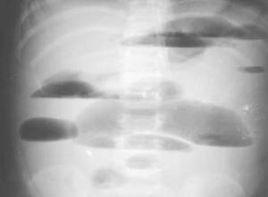

高位小腸梗阻嘔吐頻繁而腹脹較輕,低位小腸梗阻則反之,結腸梗阻的臨床表現與低位小腸梗阻相似,但X線腹部平片檢查則可區別小腸梗阻是充氣之腸袢遍及全腹液平較多,而結腸則不顯示,若為結腸梗阻則在腹部周圍可見擴張的結腸和袋形小腸內積氣則不明顯。